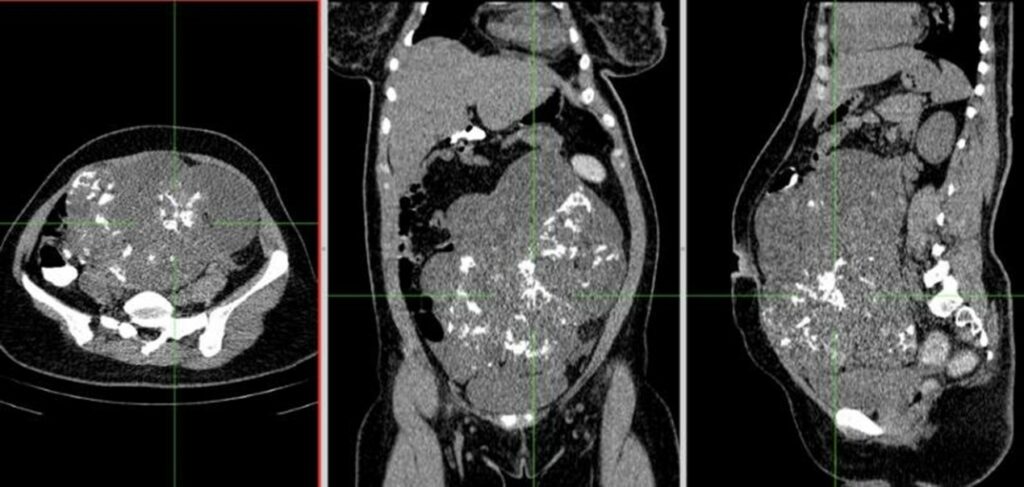

近期聽聞有位朋友的女朋友,年紀約三十歲左右,因為腹脹、痛前往急診就診,觸摸到腹部有一顆突起的腫瘤,超音波一照下去竟是一顆大於十五公分的卵巢腫瘤。後續再安排照過電腦斷層後,才懷疑是一顆惡性的畸胎瘤,也稱為不成熟畸胎瘤(Immature teratoma),需要緊急處置,其實這位女性她在腹痛的症狀出現之前,也有去一般診所就診過,但並未發現問題。